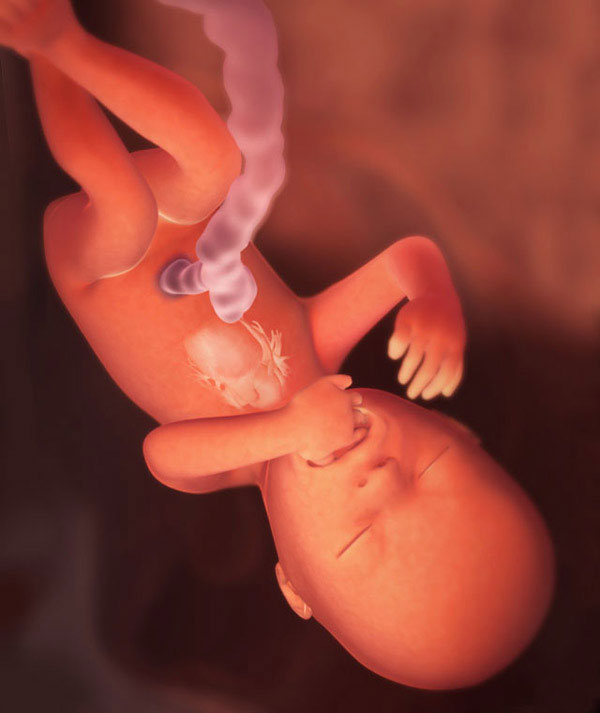

16-17 недель беременности: развитие малыша

Раздел: Житейские мотивы